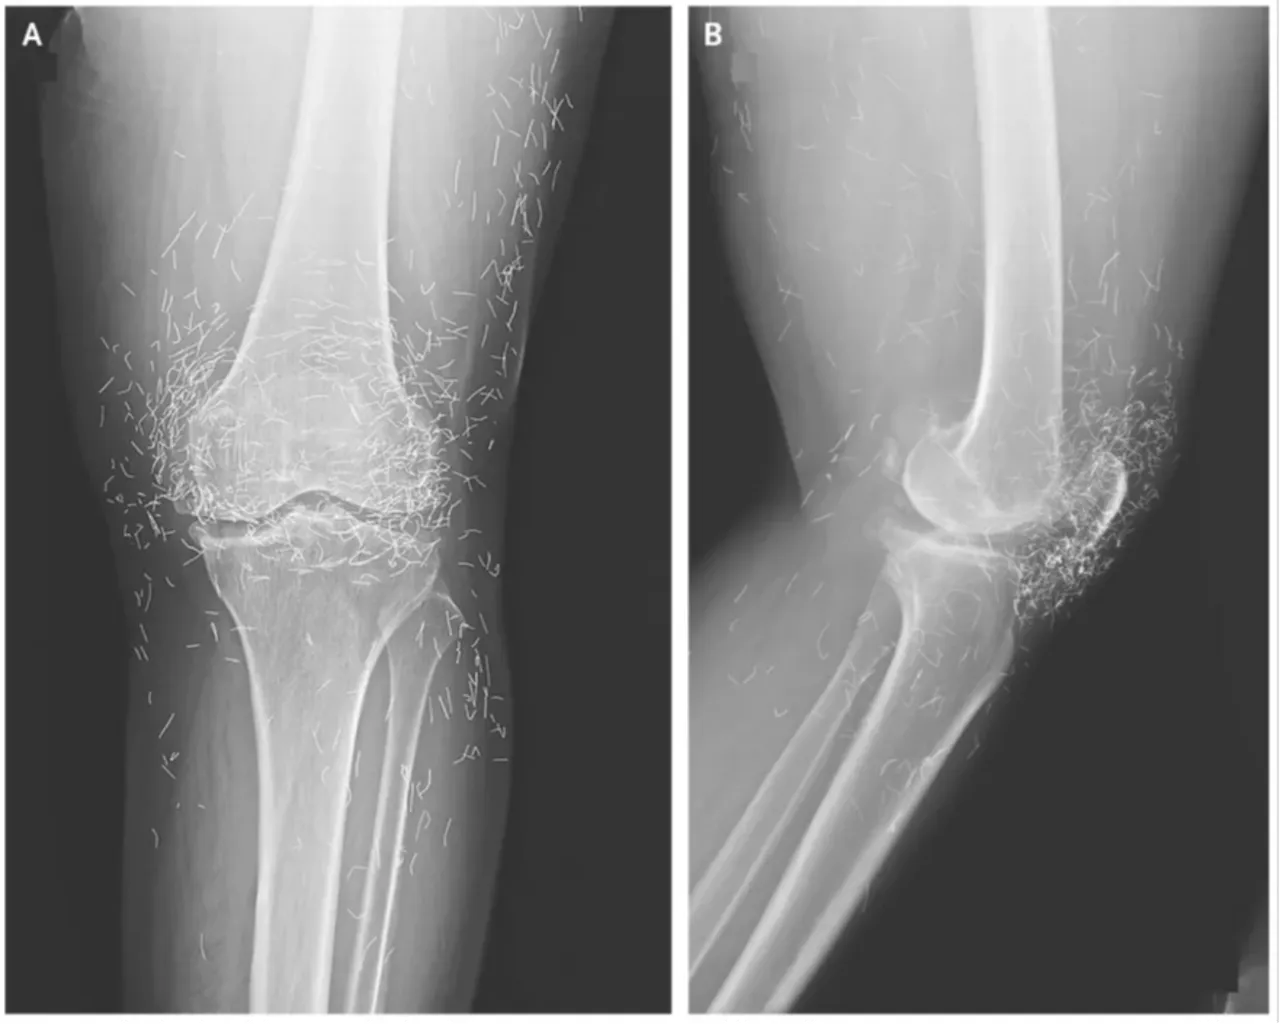

AKUPUNKTUR BEKLENMEDİK SONUÇ DOĞURDU

Eklem ağrıları için akupunktur yaptıran bir kadının dizlerinde ciddi kemik değişimleri tespit edildi. İncelemelerde, tedavi sırasında diz içine bırakılan metal ipliklerin eklem yapısına zarar verdiği ortaya çıktı. Vaka, alternatif tedavilerin kontrolsüz uygulanmasının risklerini gündeme getirdi.